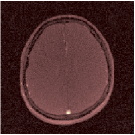

VI-E In-vivo experiments

Two sets of experiments were conducted here: first, we used the 2D and 3D acquisition sequences for scanning a healthy volunteer’s brain (real-world acquisitions). Figures 6 and 7 display the parametric maps reconstructed from 2D spiral and radial readouts. We computed the T1, T2 and proton density (PD) maps using baseline reconstruction algorithms ZF, VS, LR, FLOR, AIR-MRF and our proposed LRTV. While baselines use DM either for quantitative inference or also during reconstruction (i.e. AIR-MRF), we further compare the DM-free LRTV’s performance when cascaded to DM, KM and MRFResnet for quantitative inference. For the 3D spiral acquisitions we compared LRTV and its closest competitor VS in Figure 8. Outcomes from other tested algorithm are displayed in the supplementary materials (Figure S5). Since FLOR does not use dimensionality-reduction, our system ran out of memory during 3D reconstruction; hence results are not reported in this case.

VI-E1 Discussion

The LRTV-DM and LRTV-MRFResnet perform on par, and both outperform all tested baselines for reconstructing T1, T2 and PD maps in all acquisition schemes. This can be observed both visually in Figures 6, 7, 8, S2 and S3, and quantitatively in Table IV across all tested metrics. Other baselines were unable to successfully remove the under-sampling artefacts in TSMIs, and these errors propagated to the parameter inference phase and resulted in inaccurate maps. Temporal-only priors incorporated within LR are shown insufficient to regularise the inverse problem and LR sometimes (e.g. 2D spiral acquisitions) can admit solutions with even stronger artefacts than the model-free ZF baseline. This issue was previously studied for other non-Cartesian MRF readouts that similar to our spiral/radial trajectories, miss to sample the corners of the k-space in all timeframes (see section 2.2.2 and figure 2 in [19]). In the absence of reference for the k-space corners information, the LR iterations despite minimising the objective can converge to solutions with high-frequency artefacts, as visible in the computed maps. This highlights the need for adding an appropriate spatial-domain regularisation. FLOR reduces the LR’s artefacts but this improvement is limited because the suggested nuclear norm penalty does not incorporate an explicit spatial regularisation. Further for reducing artefacts, FLOR can introduce an undesirable bias in the computed T1/T2 maps e.g. see error maps in Figures S2 and S3. The non model-based VS baseline incorporates spatial regularisation and results in spatially smoother maps than ZF and LR, but it is unable to output artefact-free images. Further and consistent with our in-vitro experiment, we observe that VS overestimates the T2 values (e.g. in White and Grey matter regions) in tested 2D acquisitions i.e. the spatial regularisation trades off agains the quantification accuracy. The model-based AIR-MRF adds spatial regularisation through 2D/3D low-pass Gaussian filters however this trades off the sharpness of the computed maps and can increase the errors at the tissue boundaries (we searched Gaussian spreads that keep the blurs and high-frequency artefacts minimal). For our acquisition readouts, Gaussian filters performed better than disk filters of [19] for avoiding strong Gibbs artefacts. On the other hand, the spatiotemporally regularised LRTV greatly improves the TSMI reconstructions i.e. 4 dB enhancement compared to the closest competitor baseline (Table IV). This enables computing accurate and aliased-free multi-parametric inference using DM or the DM-free learning-based alternative MRFResnet as visible in Figures 6, 7, 8, S2 and S3. MRResnet and DM score competitive quantitative inference results i.e. T1 and T2 MAPE less than 5% and 9%, respectively (Table IV). KM also outputs comparably accurate T1 maps, however this shallow learning model despite having a model size larger than MRFResnet, is unable to learn accurate T2/PD quantification and it results in poor estimated maps, consistent with our observations in section VI-C.